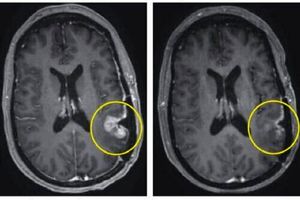

بیشتر بخوانید[ad_1] به گزارش طلوع شرق پژوهشی تازه مشخص می کند که پزشکان بهزودی میتوانند از هوش مصنوعی (AI) برای تشخیص